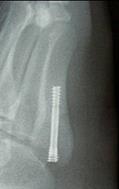

骨癒合が不良のときは、低周波や超音波による骨癒合促進刺激を実施し経過観察となりますが、多くは、癒合を促進するためにスクリューを埋め込みます。